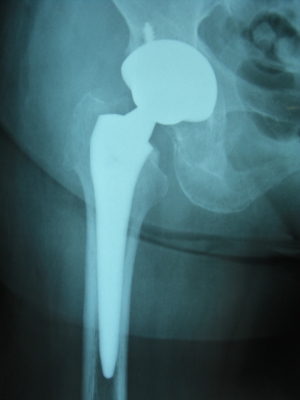

50歳 変形性股関節症 MIS-DAによる人工股関節置換術

術後3日目に歩行訓練開始し術後2週で杖なし歩行で退院

58歳 大腿骨頭壊死 MIS-DAによる右人工股関節置換術

術後2日で離床、3日めに歩行器歩行訓練開始、5日で杖歩行、7日で杖なし歩行可能となり2週で退院

86歳 続発性変形性股関節症 MIS-DAによる右人工股関節置換術

術後3週で杖歩行により退院